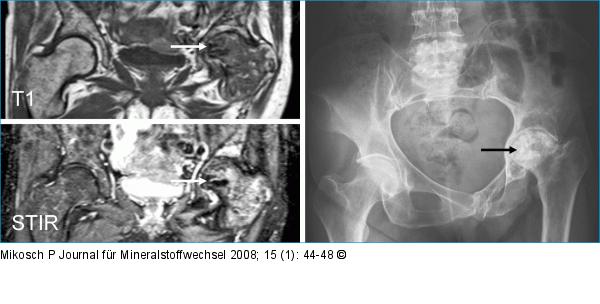

Abbildung 2: Hüftkopfnekrose MRI T1, STIR und Röntgenübersicht Beckenregion: Avaskuläre Hüftkopfnekrose links mit sekundärer Defomierung und sklerotisch, degenerativen Veränderungen des Hüftgelenkskopfes (Pfeil). |

Abbildung 2: Hüftkopfnekrose

MRI T1, STIR und Röntgenübersicht Beckenregion: Avaskuläre Hüftkopfnekrose links mit sekundärer Defomierung und sklerotisch, degenerativen Veränderungen des Hüftgelenkskopfes (Pfeil). |